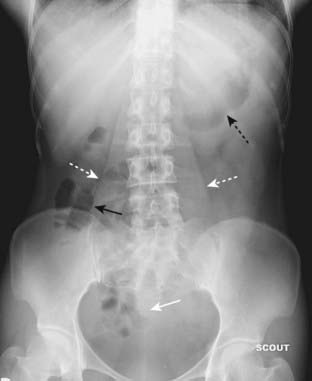

Figure 13-7 Location of large bowel.

The large bowel usually occupies the periphery of the abdomen. The small bowel is located more centrally. Here, the large bowel (solid black arrows) contains a normal amount of air. The liver occupies the right upper quadrant and normally displaces all bowel from this area.